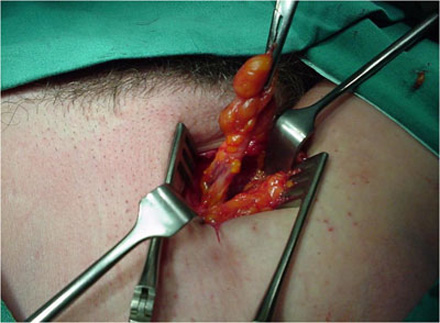

Femoral hernial sac being dissected out.